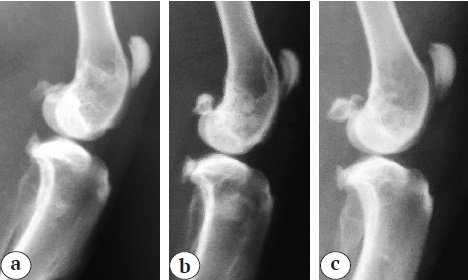

On day 84 of the experiment in Group 1, the interface between the implanted material and the host bone was diffuse in 50% of cases. Xenomaterial was only visible in the proximal metaphysis of the tibia. In Group 2, the implant was well visualized in 90% of cases and the contour of the host bone defect was well defined by that date. In Group 3, the material was completely resorbed in 33% of cases and the borderline of the host bone defect was not visible by that date.

At day 182 of the experiment, traces of implanted material were visible in Group 1. In Group 2, the first X-ray signs of BM remodeling appeared only by that time. We noted the reduction of implanted material volume, blurring of the borderline of the bone defect. However, high density of the implant was preserved. In Group 3, the borderlines of the bone defect were not visible by that time (Fig. 2).

Fig. 2. X-rays of the implantation area on the 182nd day after implantation: a — Group 1; b — Group 2; c — Group 3

Thus, it can be noted that X-ray signs of material replacement in Groups 1 and 3 were comparable and appeared by day 182 after implantation. There was no complete material replacement by the last day of the follow-up in Group 2.